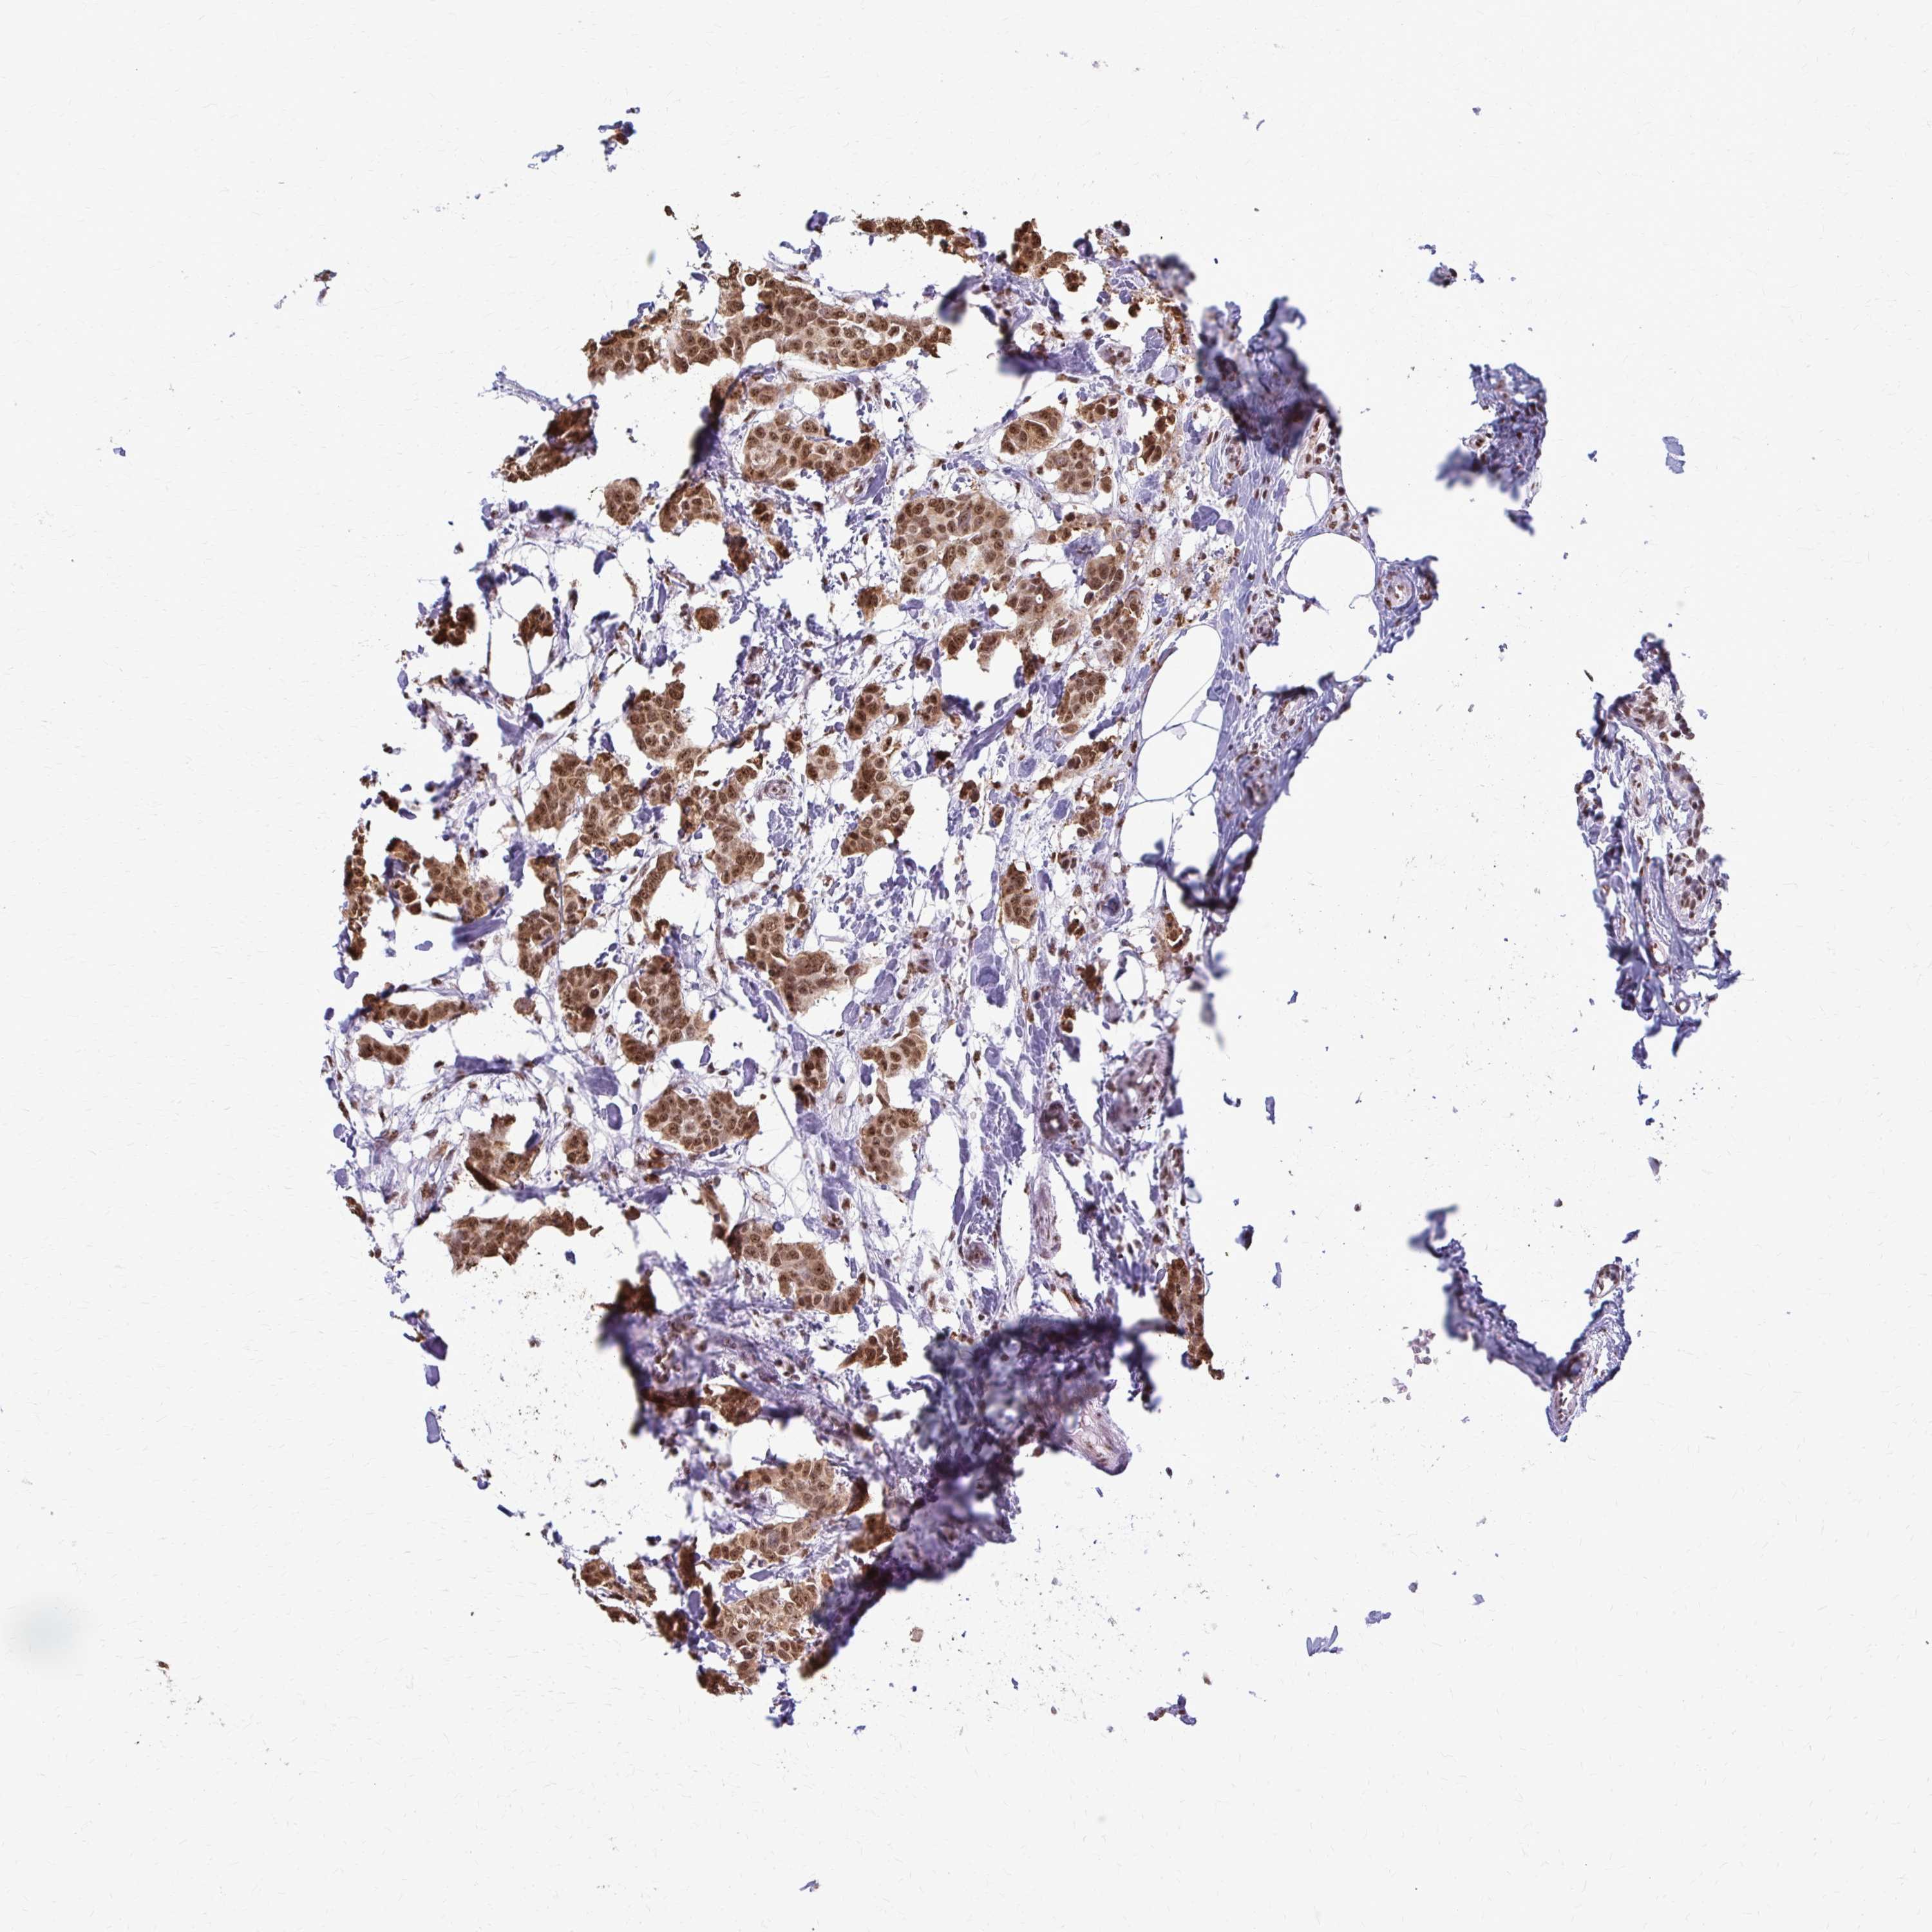

BRCA TCGA BRCA VALIDATION PROTEIN EXPRESSION